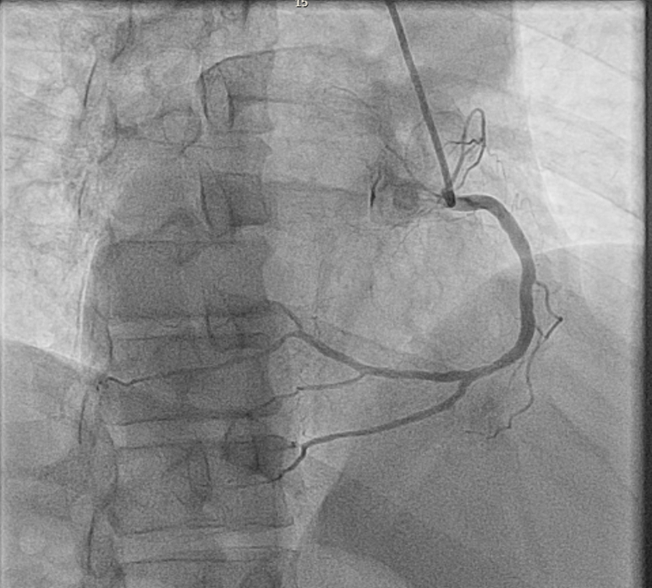

A coronary angiogram from the right radial with a 6 French Tiger Radial Catheter in the right anterior projection (RAO) 30 degrees showed minor luminal irregularities in the RCA, and 90% stenosis in the LAD. RCA was enganged anticlockwise and LCA clockwise.

Engaging the coronary arteries is challenging. We used a Tiger radial catheter with a reverse torque technique: anticlockwise for the RCA and clockwise for the LCA. Both arteries were engaged in the right anterior oblique view at 30 degrees. The cranial and caudal angulation remained the same, but the standard left anterior oblique view was switched with the right anterior oblique view and vice versa. The double inversion technique is useful during interventions when dealing with unfamiliar anatomy. It is not well-established whether dextrocardia is a risk factor for myocardial infarction.